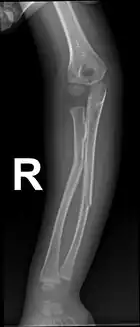

Greenstick fracture

| Greenstick fractures on X-ray. | |

A greenstick fracture is a fracture in a young, soft bone in which the bone bends and breaks. Greenstick fractures occur most often during infancy and childhood when bones are soft. The name is by analogy with green (i.e., fresh) wood which similarly breaks on the outside when bent.